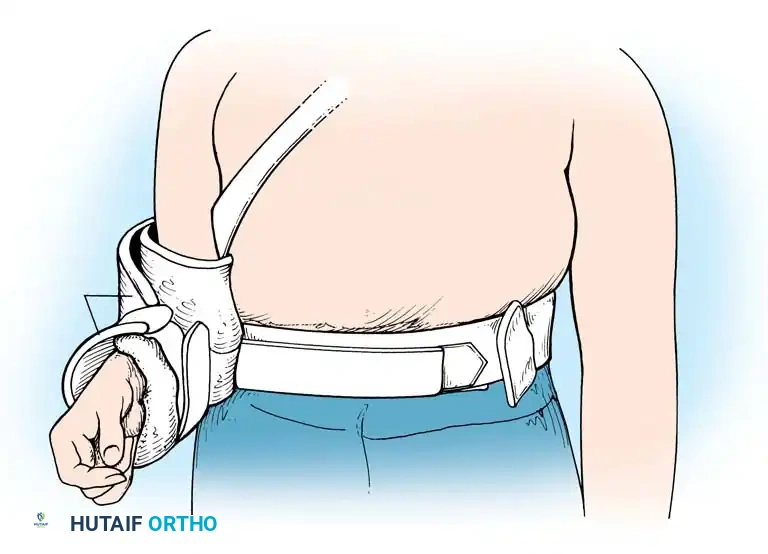

Postoperative Protocol and Rehabilitation

Successful surgical stabilization is heavily reliant on a structured, phased rehabilitation program that protects the healing capsulolabral tissues while preventing debilitating stiffness.

Phase I: Protection (Weeks 0-4)

* The shoulder is immobilized in a sling, often with a small abduction pillow to relieve tension on the superior repair.

* Pendulum exercises and passive forward elevation (up to 90 degrees) are initiated.

* External rotation is strictly limited to neutral (0 degrees) to protect the anterior capsular repair and subscapularis.